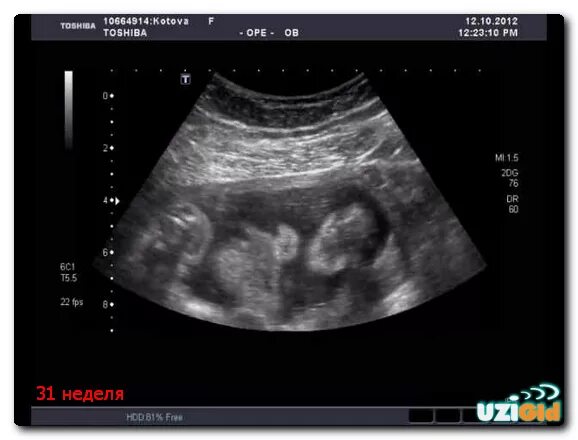

Девочка 30 недель